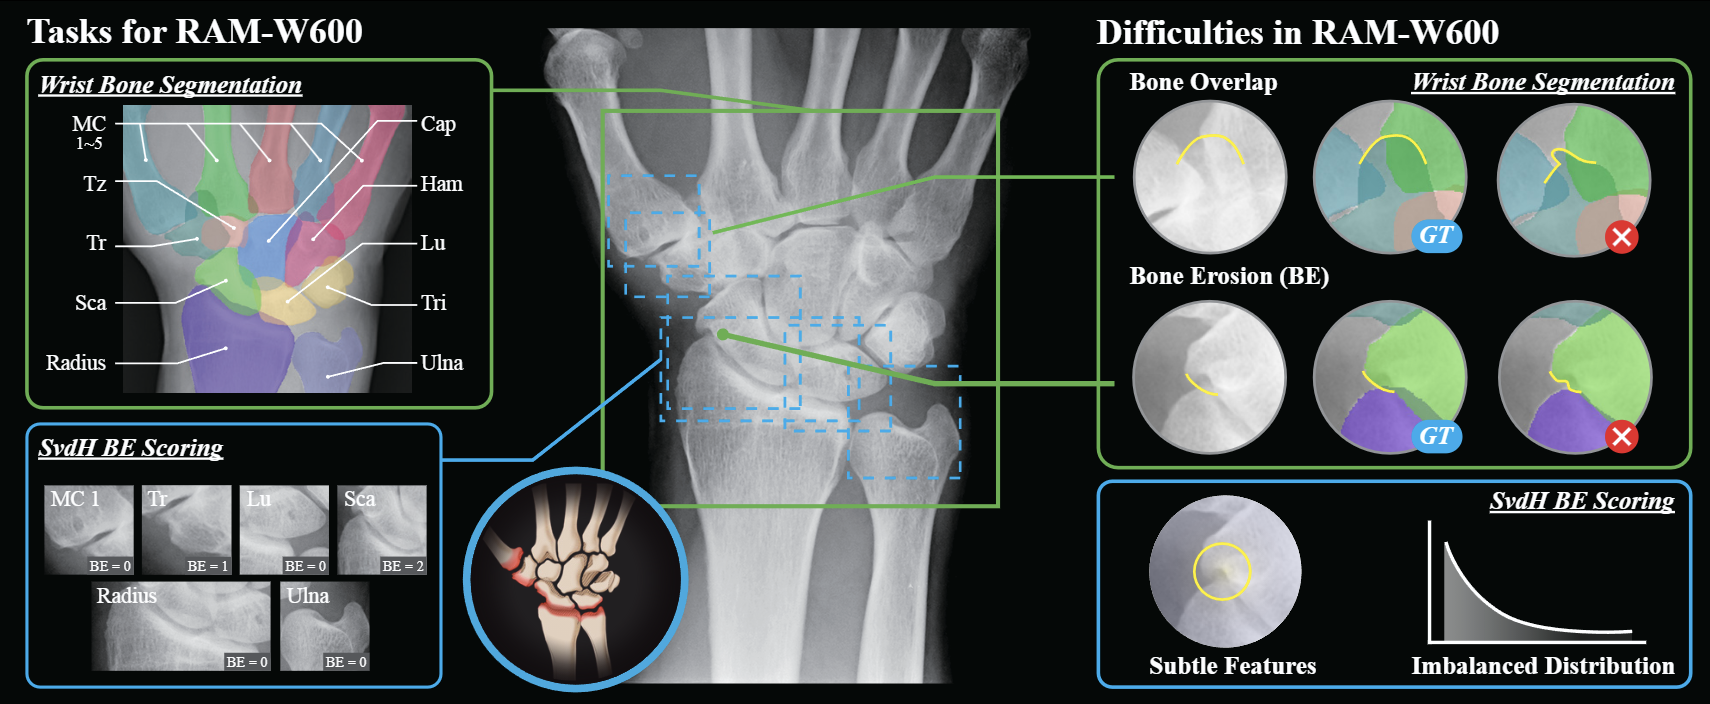

Computer-Aided Diagnosis for Hand Rheumatoid Arthritis

BIBM2025, NeurIPS2025